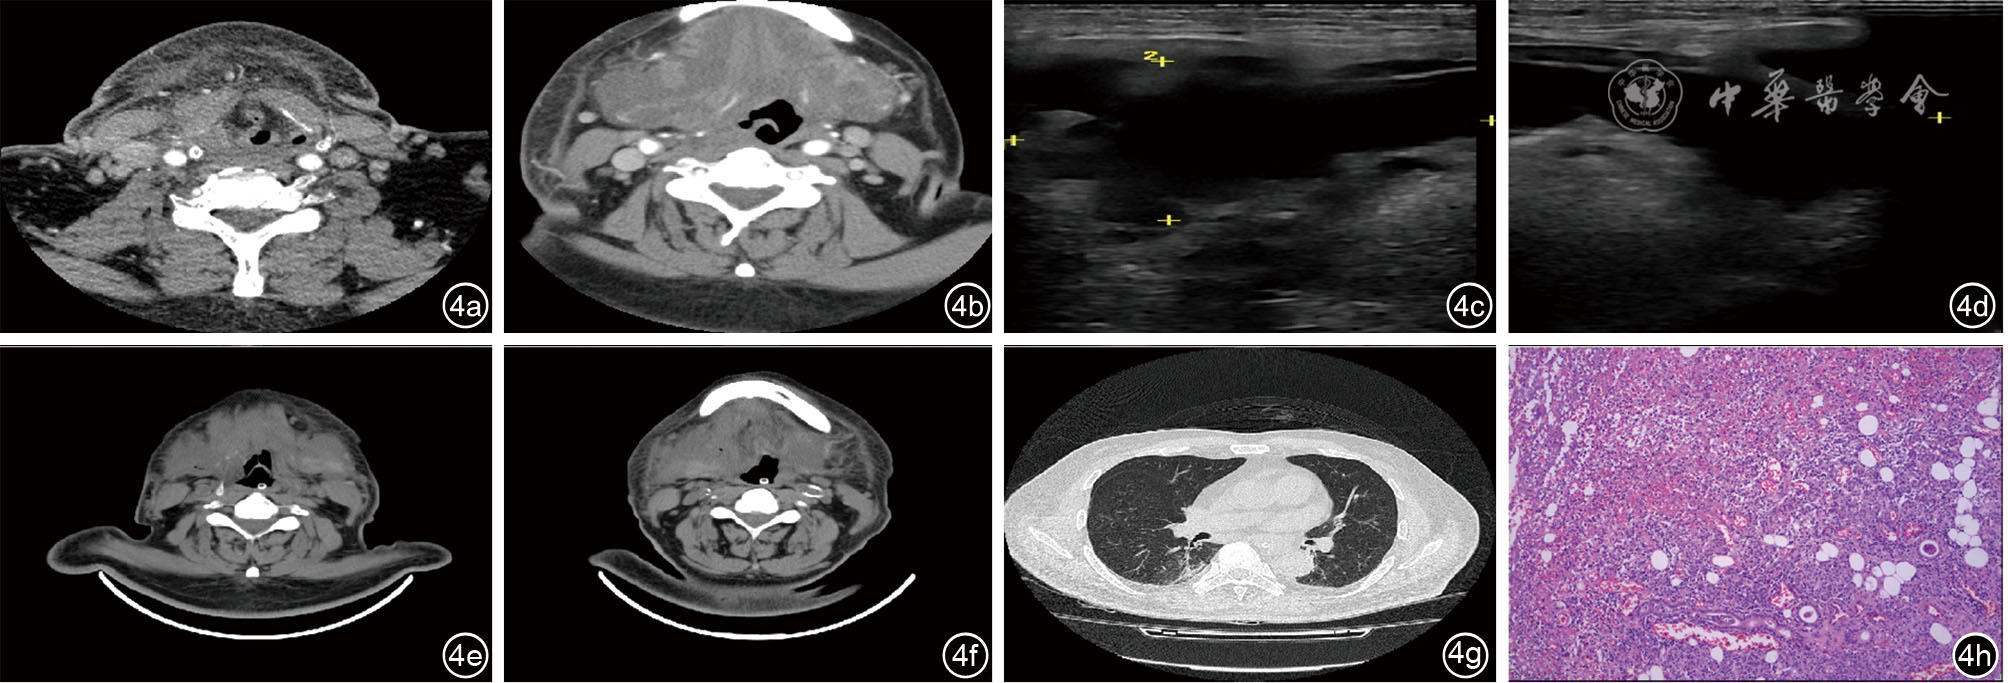

图4 病例四患者影像病理学资料。图4a~4b为颈深间隙感染患者术前颈部CT;图4c~4d为术前颌下腺彩超;图4e~4f为术后颈部CT;图4g为术后胸部CT;图4h为术后常规病理切片

4 男性 62 颌下腺脓肿,颌下间隙感染,急性呼吸衰竭,急性心力衰竭,吸入性肺炎,贫血,消化道出血,2期糖尿病肾病,慢性肾脏病5期,高血压3级(极高危),急性呼吸窘迫综合征(中度) 两侧颌下及刻下探及不规则液性暗区,范围约9.4 cm×3.7 cm,脓肿形成,双侧颈部淋巴结肿大。 经颈双侧颌下腺切除术+右侧咽旁,颌下,颏下,左侧颌下,颏下间隙脓肿切开术 (左侧颌下腺)急慢性炎,局灶化脓性炎,伴肉芽组织增生。(右侧颌下腺)急慢性炎,局灶化脓性炎,伴肉芽组织增生。 好转